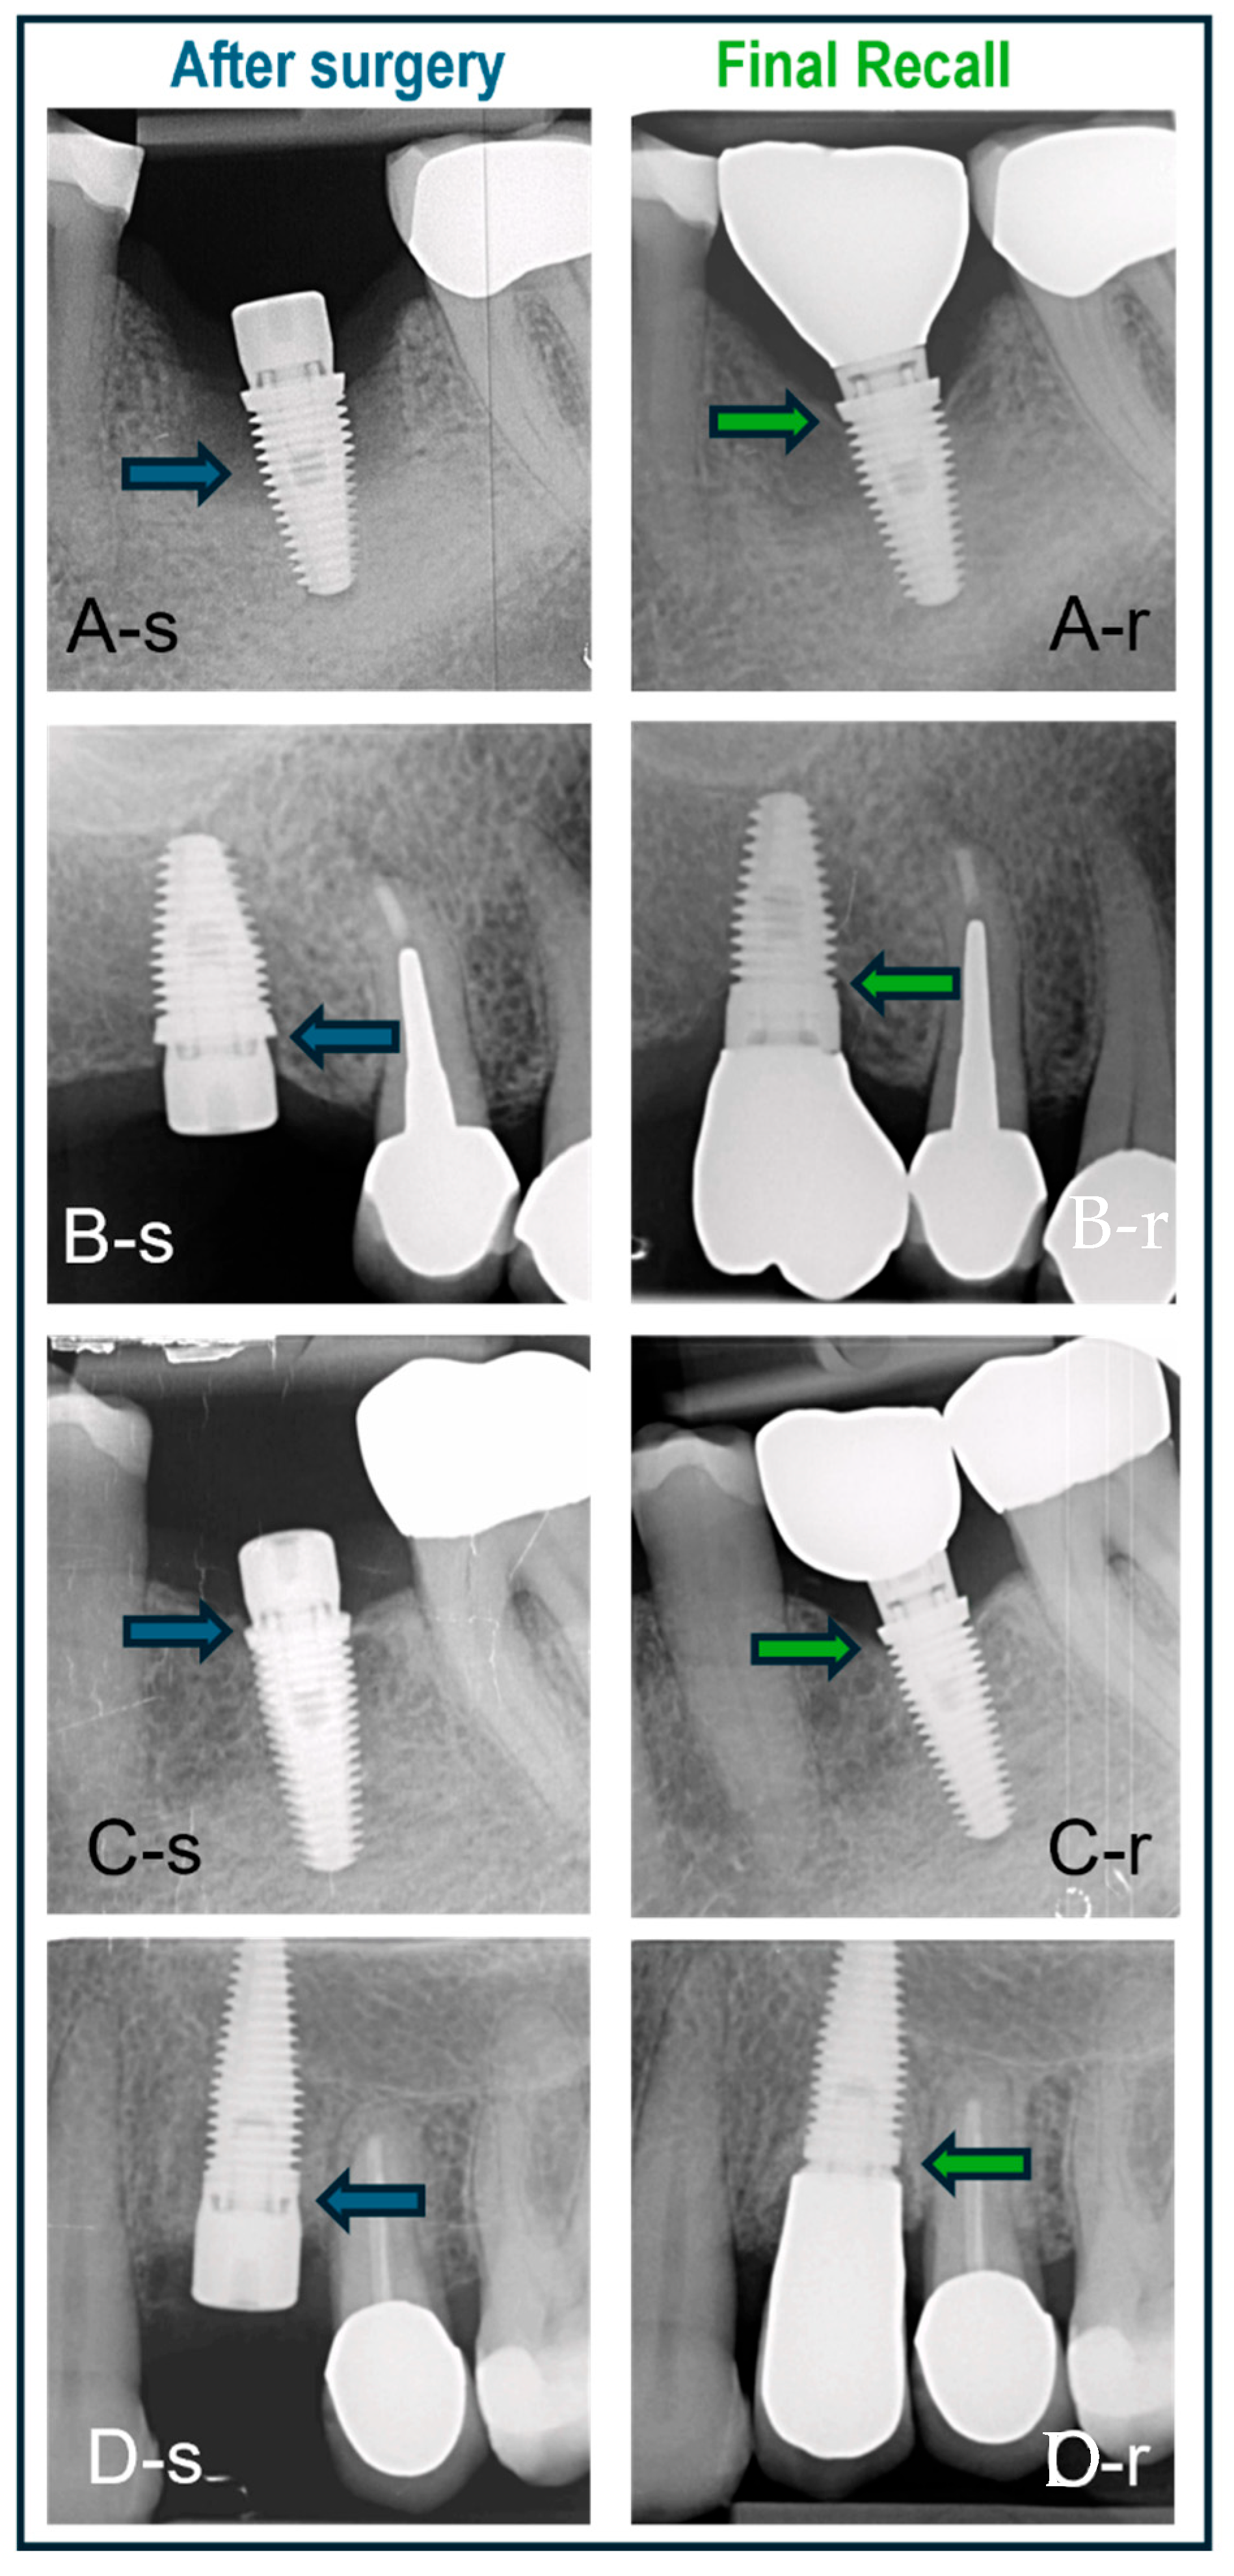

Some clinical cases representing the three surgical protocols with different implants are shown in Figure 7.

Figure 7. Cases treated with various surgical protocols with baseline (-s) and final recall (-r) radiographs. The blue and green arrows indicate bone level at baseline and recall, respectively. (A) Immediate placement of a lower molar using a BAT implant placed in an intact socket without guided bone regeneration; bone regrowth and bone maturation in the socket are evident. (B) BAT implant placed flaplessly in healed bone followed by minimal bone remodeling; non-platform switched crown. (C) BAT implant with open flap followed by installation of platform-switched crown and minimal bone remodeling. (D) IBT implant placed in healed bone and restored with non-platform-switched crown and no signs of bone loss.